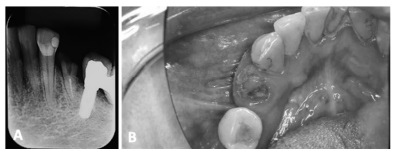

Com base no caso clínico descrito, julgue o item subsecutivo.

A remoção da raiz residual, demonstrando uma apreensão satisfatória, poderia ocorrer por meio da técnica primeira com uso de fórceps 151, cujo formato permite a mobilização radicular.